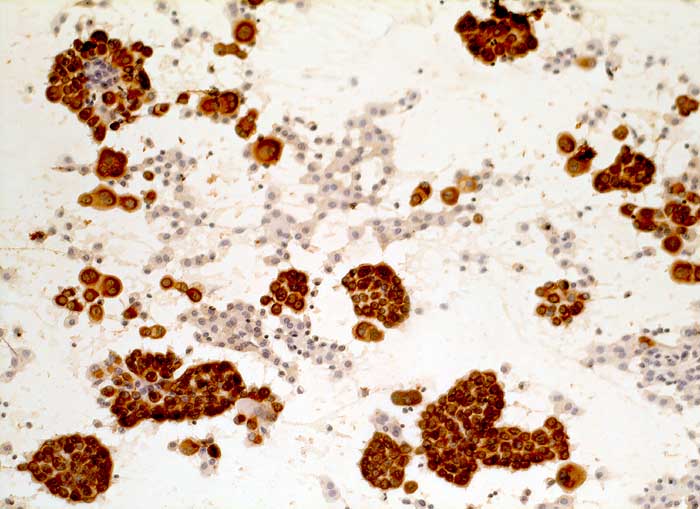

CK22 und Lu-5 repräsentieren Zytokeratingemische, welche einen Grossteil normaler und neoplastischer Epithelzellen anfärben.

Reaktion in Neoplasien:

Die meisten Karzinome und vereinzelte Sarkome reagieren positiv mit diesen Panzytokeratinen. CK22 ist etwas sensitiver und spezifischer als Lu-5. Entdifferenzierte oder sarkomatoide Karzinome können die Positivität für Zytokeratine verlieren.